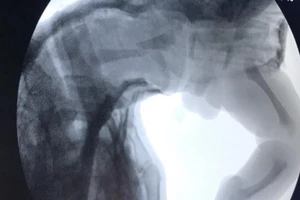

Lý do BV Chợ Rẫy xuyên đinh nhầm chân bệnh nhân đau cột sống